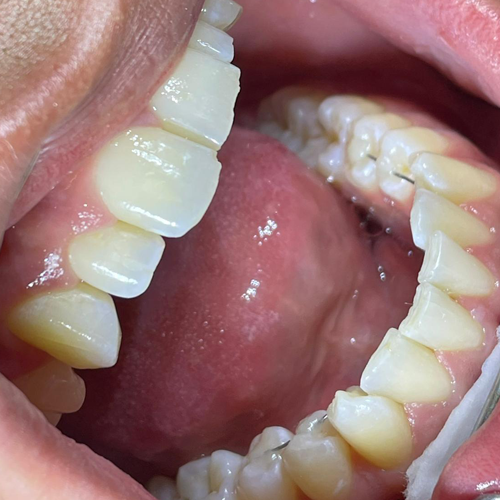

Comprueba en la práctica cómo el conocimiento se transforma en resultados reales a través de los casos de nuestros alumnos.

SALA DE PROCEDIMIENTOS

Siga clases prácticas y la evolución de casos clínicos reales directamente desde la clínica del Dr. Ary Nunes.